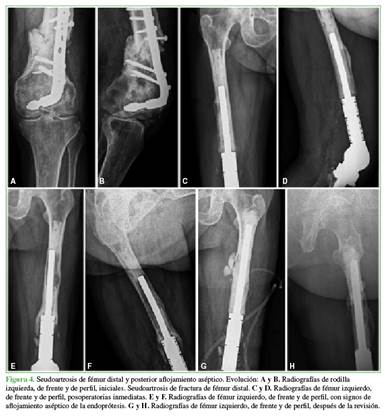

Según las radiografías, ningún paciente tenía signos de infección, aflojamiento del material, rotura de la prótesis, fractura periprotésica ni ningún otro signo de falla del implante en el momento del análisis. Cabe destacar que, en el paciente 9, se evaluaron también las radiografías anteriores a la revisión, donde se constataron signos de aflojamiento aséptico (Figuras 4 y 5).

En cuanto al aflojamiento aséptico de las endoprótesis en el tratamiento de enfermedades no neoplásicas, las tasas oscilan entre el 0% y el 9,5%.4 En nuestra serie, hubo un solo caso (paciente 9) (9,1%).

En nuestra serie, se utilizó una prótesis abisagrada en siete pacientes y una prótesis con bisagra rotatoria en otros cinco. El único caso de aflojamiento aséptico (paciente 9) ocurrió con una endoprótesis abisagrada.